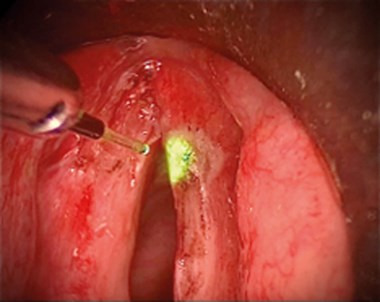

Another method of ensuring visual control of the fibre is for the surgeon to guide it with the microsuction tube in one hand and a 0º rigid endoscope in the other. This provides excellent visualisation as the endoscope accompanies the fibre directly to the point of pathology (Figure 1).

Figure 1: The laser fibre is guided with a microsurgery suction tube in the left hand and a 0º endoscope in the right for treatment – in this case, of a superficial laryngeal carcinoma.